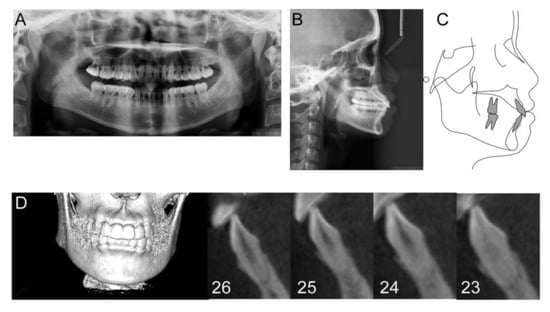

| Tooth | 26 | 25 | 24 | 23 | Mean ± SD |

|---|---|---|---|---|---|

| Lingual (mm2) | 1.49 | 1.74 | 1.82 | 1.09 | 1.54 ± 0.33 |

| Labial (mm2) | 0.68 | 1.86 | 0.68 | 0.94 | 1.04 ± 0.56 |

| Coronal (mm) | 0.40 | 0.63 | 0.30 | 2.11 | 0.86 ± 0.84 |

| Middle (mm) | 1.14 | 0.88 | 0.76 | 2.22 | 1.25 ± 0.67 |

| Apical (mm) | 0.26 | 1.14 | 0.31 | 1.87 | 0.72 ± 0.77 |